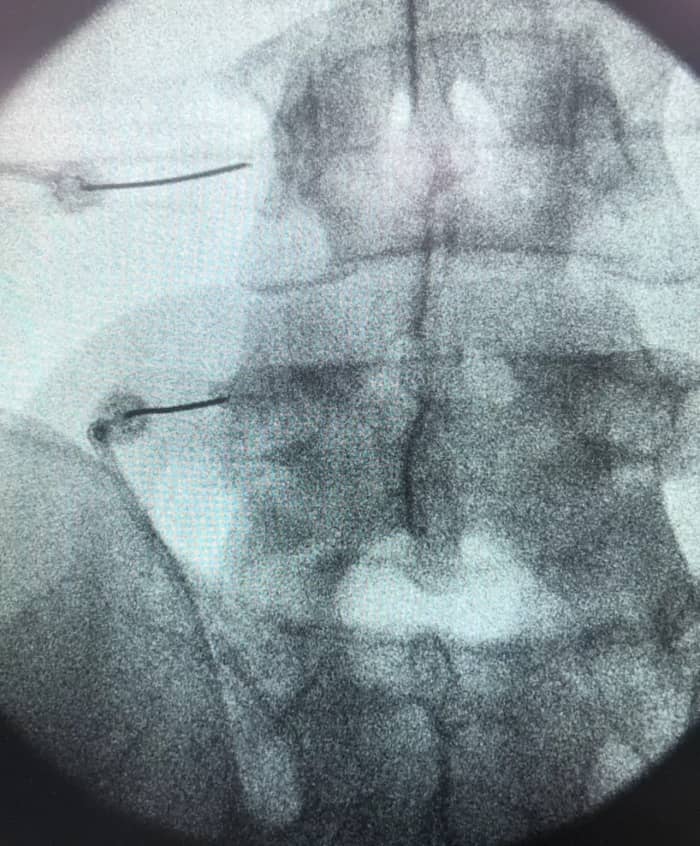

Este tratamiento se realiza mediante impulsos de radiofrecuencia, que se aplican de forma precisa en la zona afectada. A través de punciones en la columna vertebral, bajo control de rayos X y anestesia local, se busca aliviar el dolor y mejorar la calidad de vida del paciente.

La rizolisis lumbar es un procedimiento médico utilizado para el tratamiento del dolor crónico de origen facetario en la zona lumbar de la columna vertebral. Esta técnica no invasiva se realiza en quirófano, con el paciente acostado boca abajo y bajo control de rayos X.

Para llevar a cabo la rizolisis lumbar, se utilizan punciones en la zona a tratar, y mediante impulsos de radiofrecuencia, se destruyen las terminaciones nerviosas responsables del dolor en las articulaciones que conectan las vértebras lumbares.

Este tratamiento está indicado en casos de dolor crónico relacionado con lesiones articulares vertebrales y en ausencia de afectación de los nervios que se extienden hacia las extremidades. Se lleva a cabo bajo anestesia local, y en algunos casos se puede aplicar sedación si es necesario, siempre y cuando no interfiera con la cirugía.

Este procedimiento se realiza bajo anestesia local y control de rayos X para garantizar su precisión. Dependiendo del caso, podría aplicarse sedación si resulta necesario para el correcto desarrollo de la cirugía. Tras la intervención, el paciente deberá tener un breve periodo de reposo, pero podrá regresar a su hogar pocas horas después.

Este procedimiento se lleva a cabo en quirófano, bajo anestesia local y control de rayos X. Esto permite una precisión en la aplicación del tratamiento. La rizolisis puede ser realizada tanto en la zona lumbar como en la cervical, adaptándose a las necesidades específicas de cada paciente.